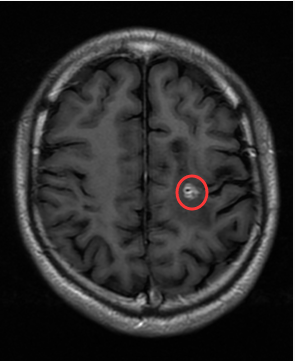

王强今年34岁 , 据他回忆 , 早在5年前 , 他就曾在深圳商场逛街时 , 突然一阵眩晕 , 随即摔倒在地 , 身体不停地抽搐 。 被朋友紧急送往附近医院后 , 又辗转了广州多家医院 , 他最终被告知颅内可能长了裂头蚴 。 这个寄生虫堪称宿主大脑区域的挖洞狂 , 只不过这一次它挖掘的区域位于王伟的功能区 , 手术风险高 , 医生建议他先保守治疗 。

这支虫子赖在了王强的功能区不走了 , 而且盘踞了五年之久 。

【核心|七八年前生吞蛇胆不下十次,而今脑内长虫险些破坏核心功能】该院接诊的神经外九科主任穆林森发现 , 患者左侧额叶有明显的占位病变且有肉芽肿形成 , 认为是裂头蚴感染的可能性较大 。 病灶位于功能区 , 稍有不慎就可能引起偏瘫 。

完善相关术前检查后 , 8月16日 , 穆林森团队在术中唤醒麻醉下为患者实施左侧额叶后部功能区寄生虫抓取术 , 将一条6cm长的活虫顺利“逮住” 。 “大约在皮下3cm的地方 , 可清晰看到有白色索条状的虫体在缓慢蠕动 。 ”穆林森说 。